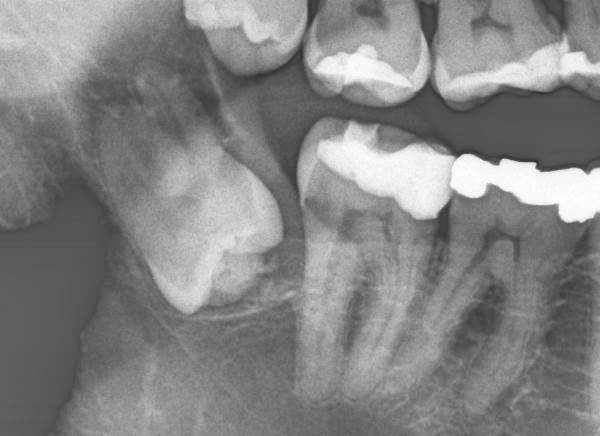

67-jährige Patientin (20.02.2024 / 7245)

Offensichtlich hat dieser Weisheitszahn die vorderen Zähne rechts unten während 36 Jahren nicht nach vorne gestossen. Um dies zu verhüten werden viele Weisheitszähne nach einer Zahnstellungskorrektur extrahiert. Doch hier ist vielmehr ein Knochendeckel über dem Weisheitszahn gewachsen.

63-jähriger Patient (30.01.2024 / 551)

Auch dieser Weisheitszahn liegt wie der obere nach 37 Jahren etwas tiefer im Knochen. Die vorderen Zähne sind etwas elongiert und abradiert.

Offenbar elongieren (und abradieren) die Seitenzähne im Laufe von 30 Jahren etwa 2 mm. Entsprechend höher wird ihre Alveole - und wächst auch neuer Knochen über dem retinierten Weisheitszahn.